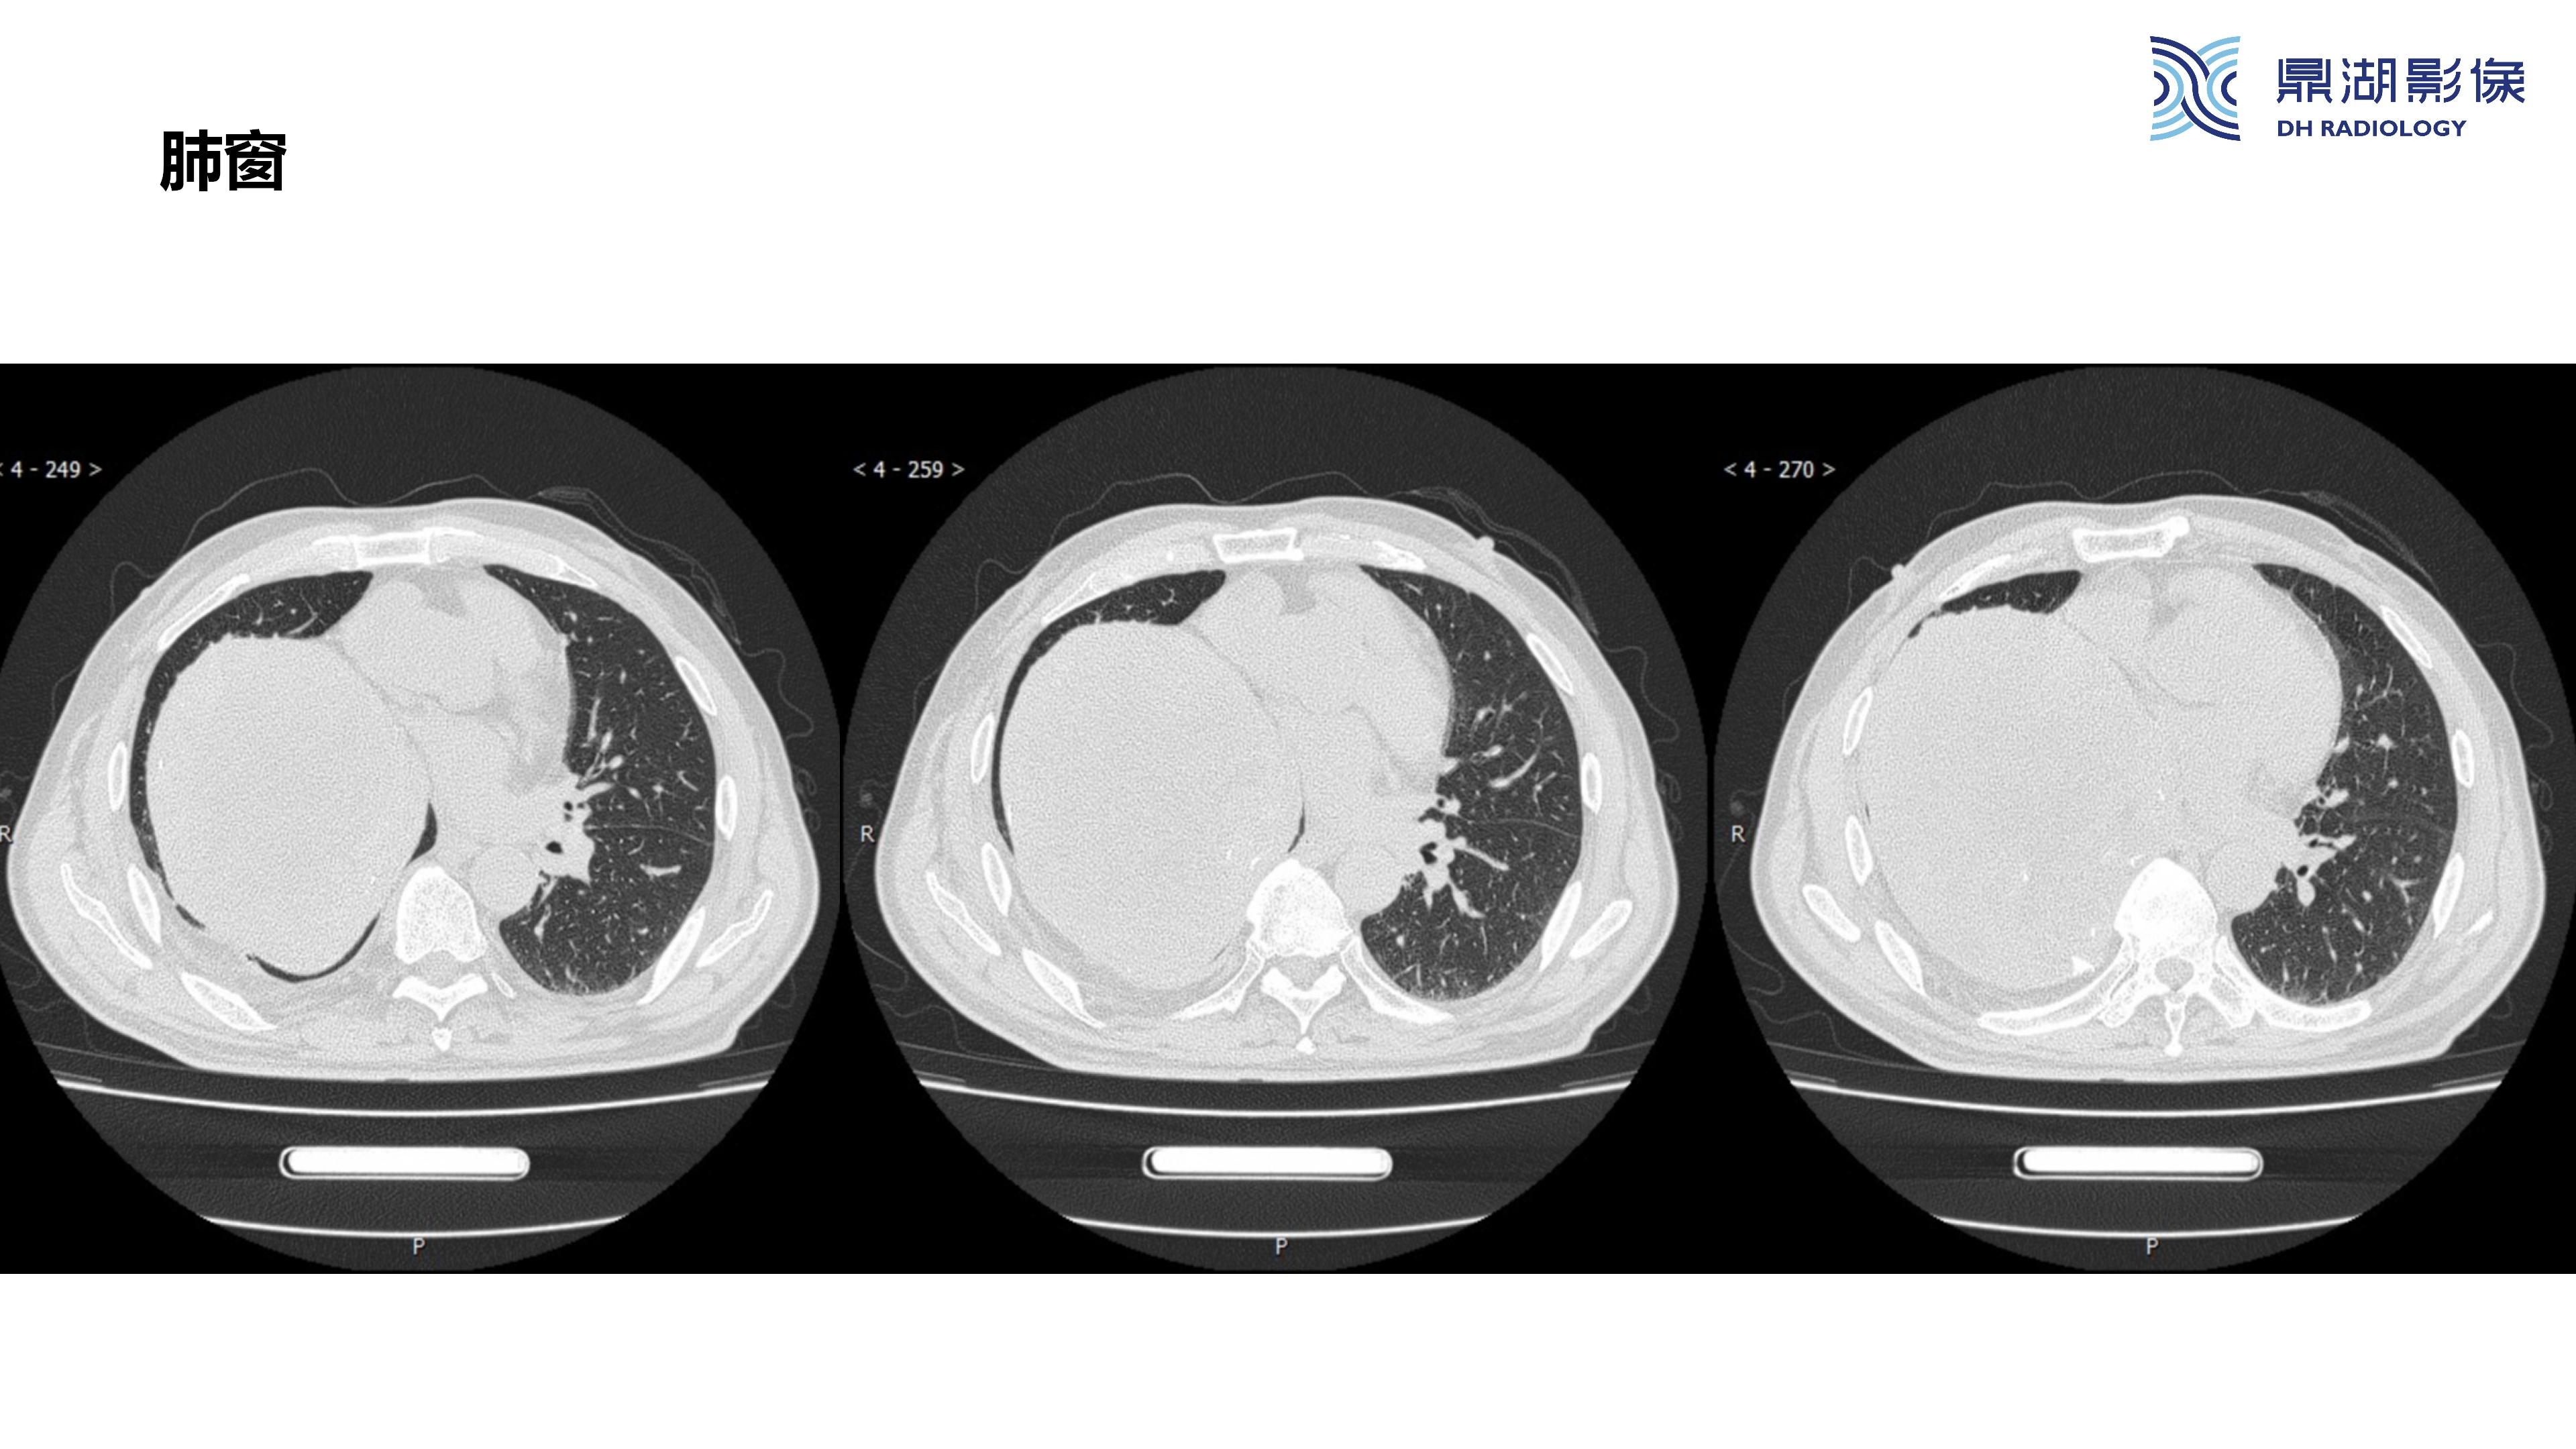

纵隔血管瘤-鼎湖社群读片病例